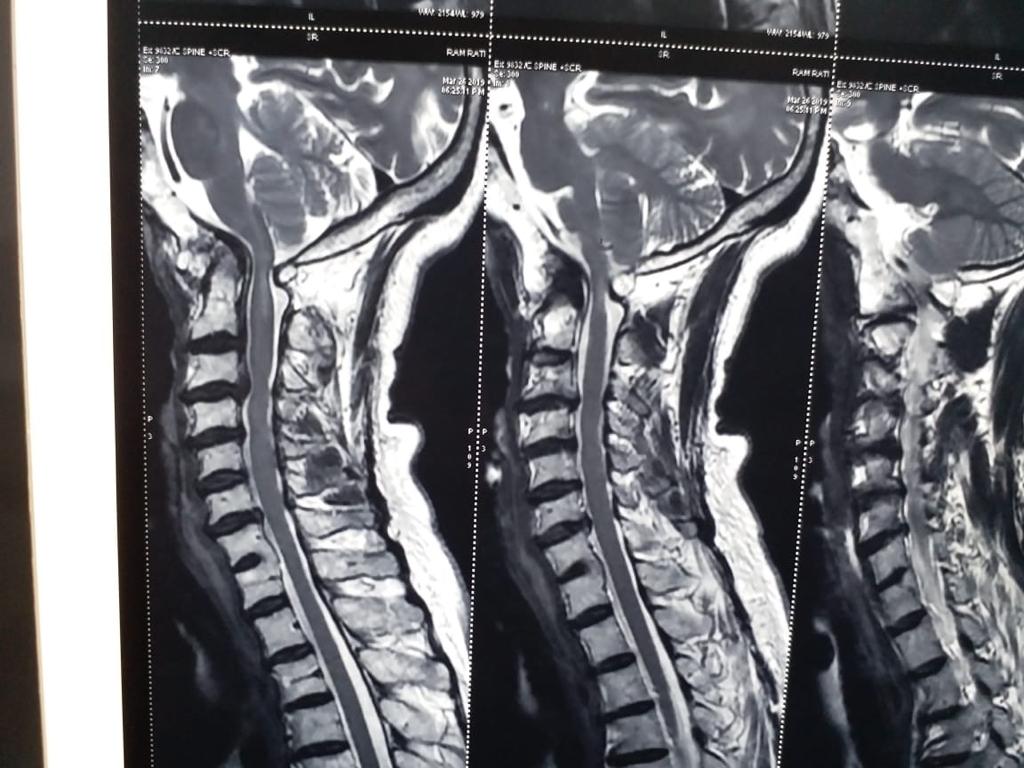

Cases